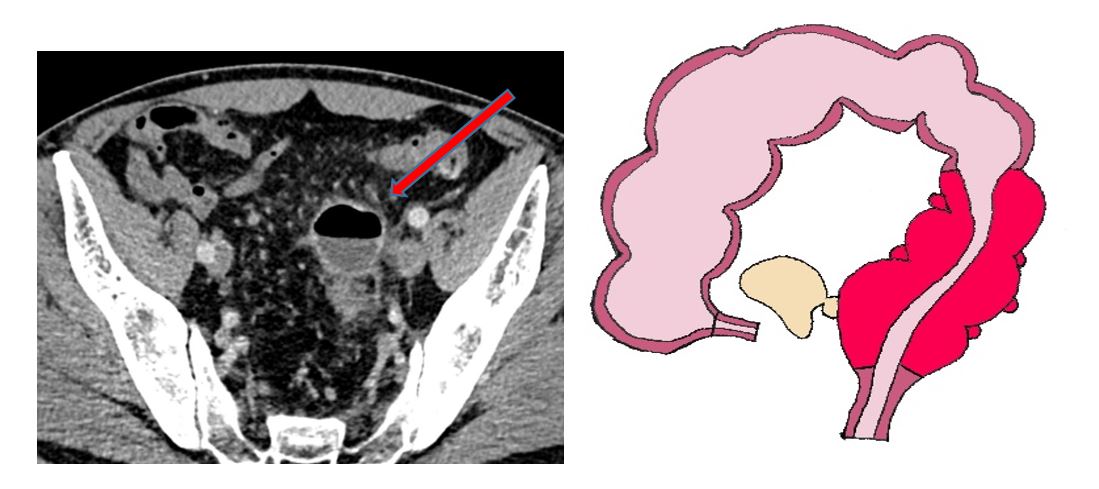

Fistule

Une diverticulite sigmoïdienne peut évoluer vers une fistule, c’est-à-dire une communication, avec la vessie. Les symptômes vont être une issue de selles par le vagin en cas de fistule entre le sigmoïde et le vagin, et des infections urinaires à répétition, la présence de gaz ou de selles dans les urines en cas de fistule entre le sigmoïde et la vessie. Un abcès peut être présent à la phase initiale. Le traitement consiste à administrer une antibiothérapie par voie veineuse (Ceftriaxone - Métronidazole) à la phase initiale en hospitalisation. La diminution des douleurs et l’amélioration du bilan sanguin sont contrôlés après 48h d’antibiothérapie par voie veineuse. En cas d’amélioration de ces deux paramètres, une sortie est autorisée avec des antibiotiques par voie orale (Augmentin 1g trois fois par jour) pour 10 jours au total. Une chirurgie sera systématiquement proposée à distance (2/3 mois après la poussée) afin de retirer le sigmoïde malade responsable de la fistule.